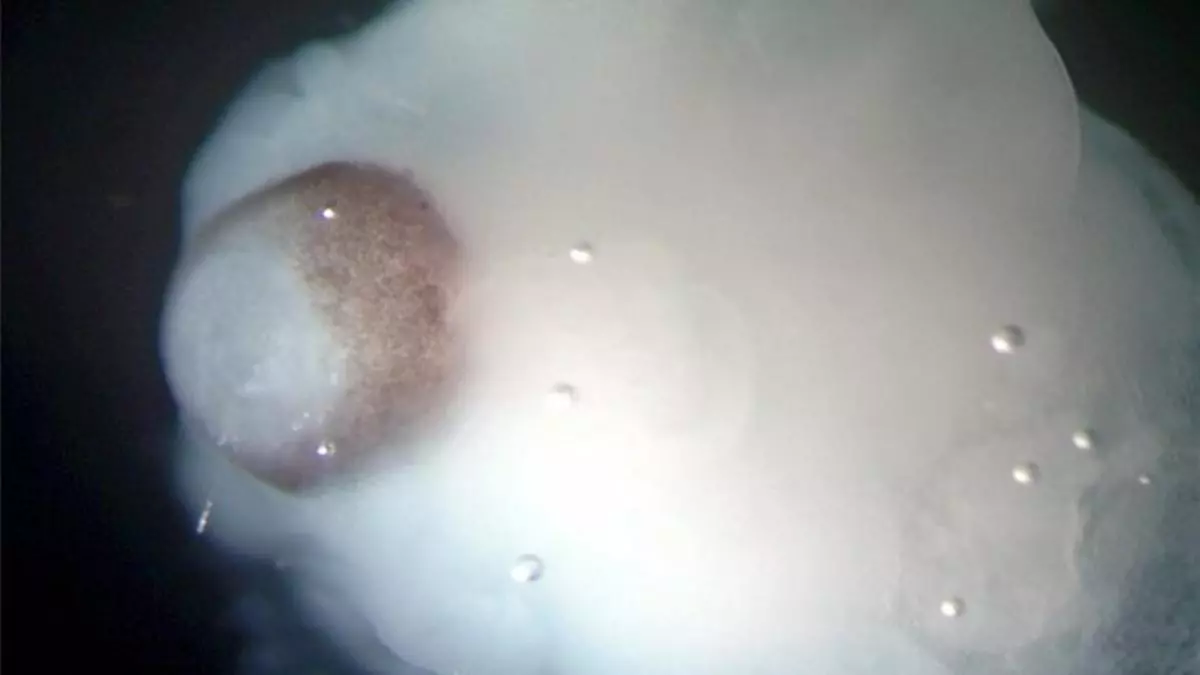

Imagen de uno de los cerebros en desarrollo creados a partir de células madre / periodico

Un equipo de científicos europeos ha desarrollado pequeños cerebros humanos tridimensionales, de cuatro milímetros de diámetro, a partir de células madre pluripotentes que ayudarán a profundizar en el estudio de las enfermedades neurológicas, informa la revista científica 'Nature'.

Estos microcerebros, que incluyen la corteza cerebral que cubre los dos hemisferios, están formados por diferentes tejidos dispuestos en capas, cuya organización guarda muchas semejanzas con la de un cerebro en sus etapas más tempranas de desarrollo.